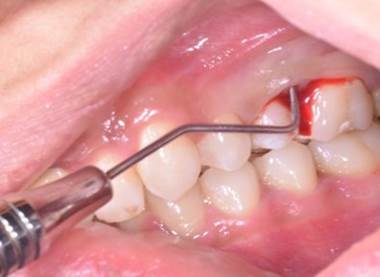

A 22-year old female patient presented in our private dental practice set up with complaint of pain, food stagnation, foul smell and loosening of couple of teeth in upper jaw. Intraoral examination revealed vertical bone loss around distal surface of upper right second premolar and mesial surface of first molar (Figure 1). The pocket depth was measured to be more than 15mm (Figure 2). The severely affected premolar and molar, on pulp testing showed pulpal involvement leading to diagnosis of endo-periodontal lesion.